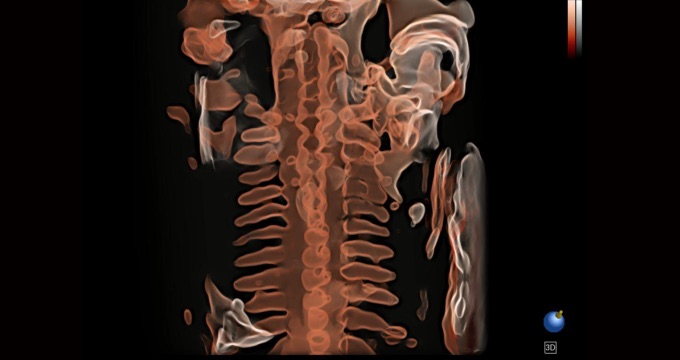

• 光影成像

三维光影成像技术采用创新性的渲染方式,增强边缘信息,使得轮廓显示更加完整,为临床提供丰富、直观的三维结构,提高临床诊断准确性。